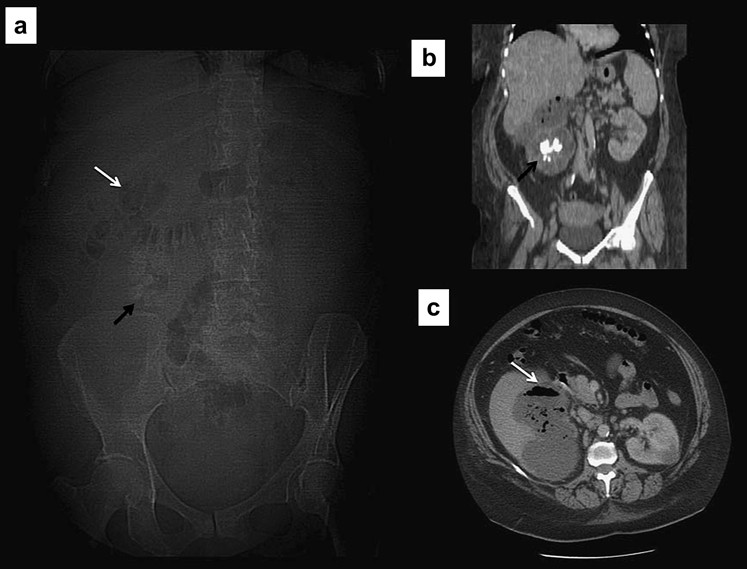

Thiếu máu ruột cục bộ

Ở người lớn, khí trong tĩnh mạch chủ yếu liên quan đến thiếu máu ruột cục bộ, tình trạng này có tỉ lệ tử vong vượt quá 50% (Hình 9). Các dấu hiệu khác trên phim X quang thường quy gồm khí trong thành ruột như miêu tả bên dưới.

Hình 9. Khí trong tĩnh mạch cửa (a) Phim X quang bụng: khí ở trong tĩnh mạch cửa (mũi tên ngắn) và tĩnh mạch lách (mũi tên dài) (b) Phim CT cho thấy khí tụ trong các nhánh cao ở gan và kéo dài tới ngoại vi (c) Phim X quang của trẻ sơ sinh cho thấy khí trong hệ cửa do việm ruột hoại tử.